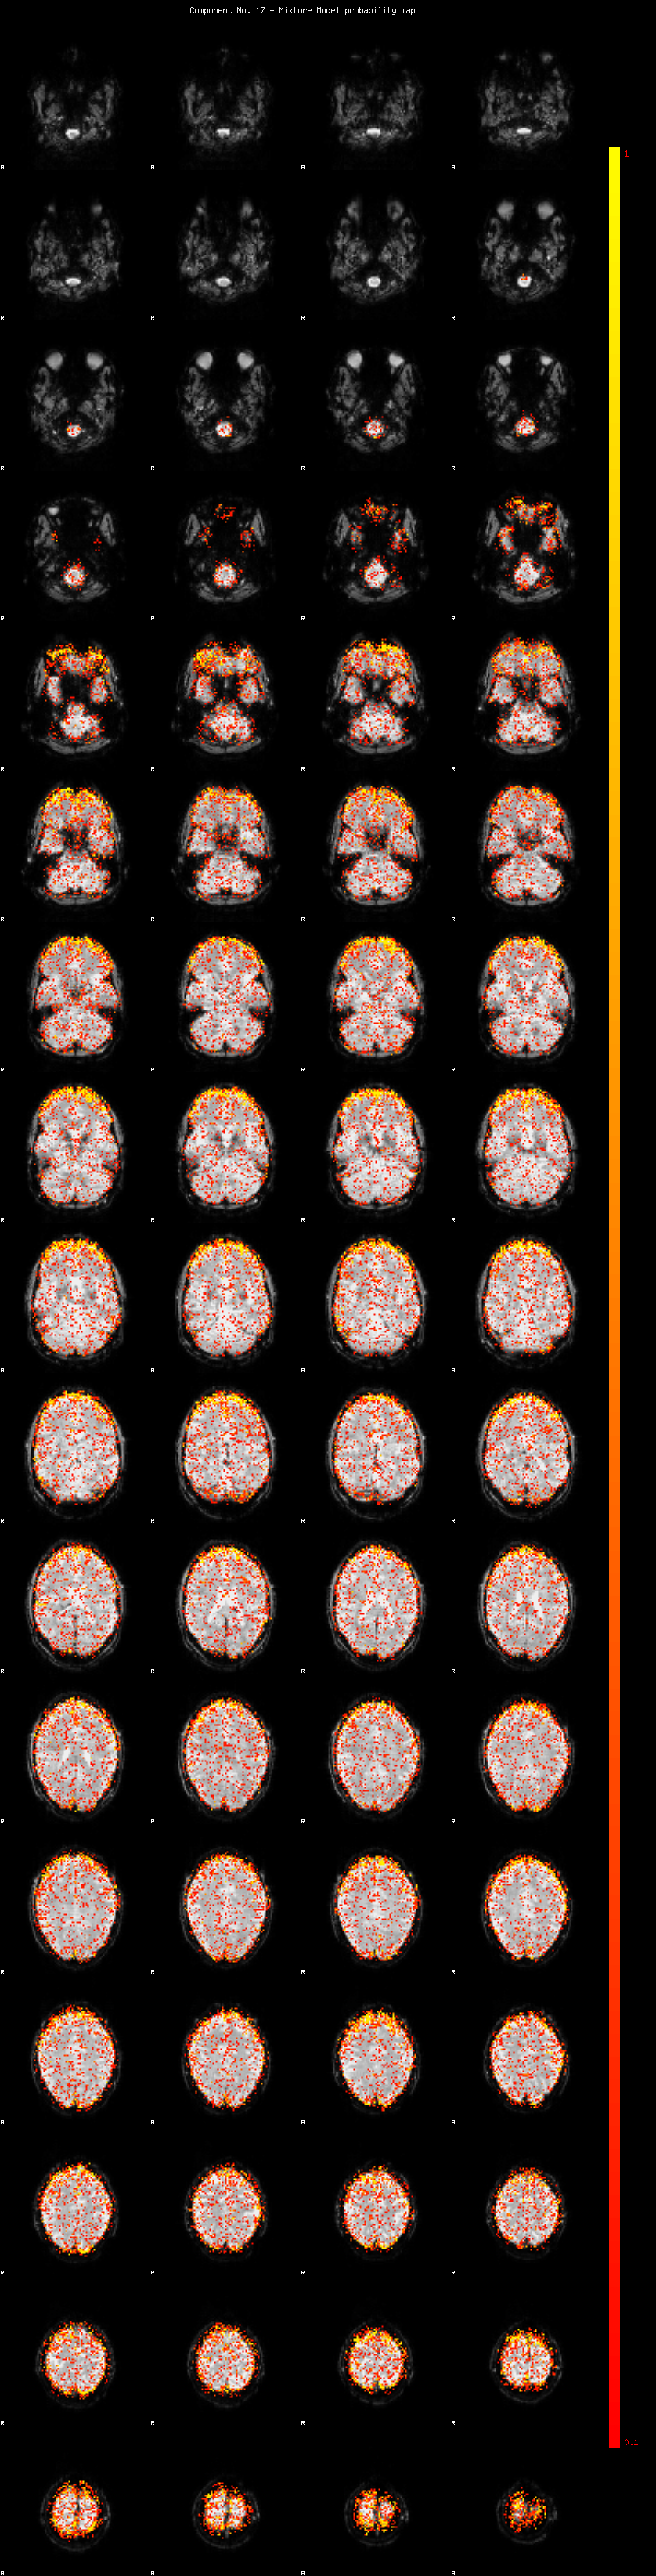

IC_17 Mixture Model fit

Means : -0.000000 2.557994 -2.398313

Vars : 1.000000 2.124937 1.708857

Prop. : 0.895122 0.064235 0.040643